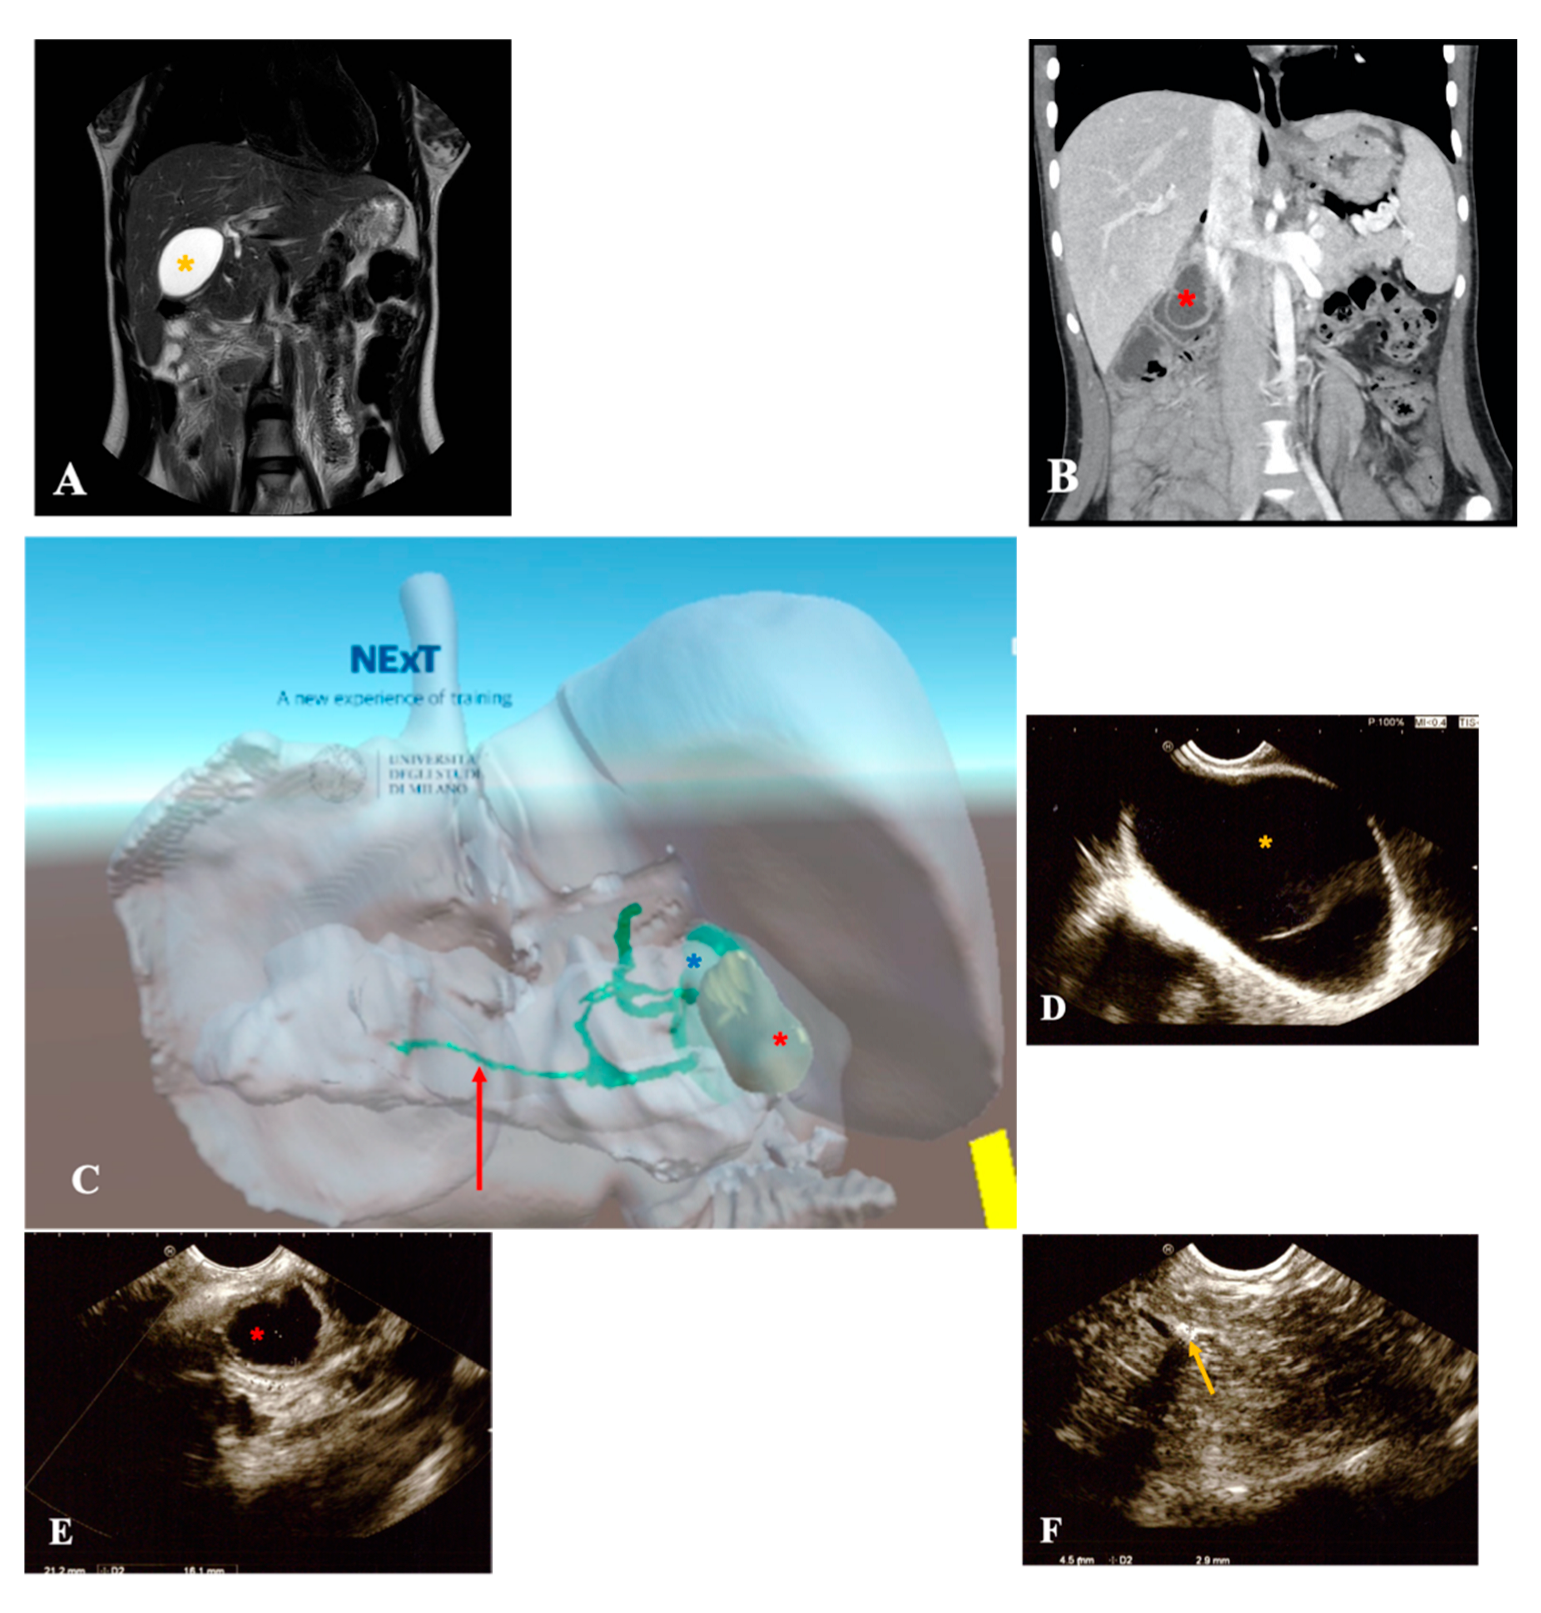

3.2.2. Biliary Tree Abnormalities

| Symptoms | Acute pancreatitis, pain in right hypochondrium | Icterus, pancreatitis | Chronic pancreatitis with choletithiasis, genetic-based | No |

| Diagnosis (prenatal evaluation yes/no) | Cholelithiasis and choledocholithiasis in duodenal atresia (duodeno-jejuno anastomosis at birth) and pancreas divisum (yes) | Choledochal cyst (Todani I) and choledocholitiasis (no) | Mutation of the gene PRSS1, Cholelitiasis, pancreatic duct duplication (no) | Gallbladder duplication Annular pancreas Duodenal duplication (yes) |

| Radiological investigations | US, MR, CT Scan, VR HMD | US, Cholangio MR | US, X-ray, Cholangio MR, CT, VR HMD | US, Cholangio MR, CT |

| Endoscopic instrumentation | EG-3870UTK Linear-Array Ultrasound Gastroscope | EBUS + Duodenoscope | Duodenoscope, EG-3870UTK Linear-Array Ultrasound Gastroscope | EBUS |

| Management | MIS (laparoscopic cholecisectomy) with LCBDE | 1. ERCP + sphincterotomy + stone removal 2. Open surgery: choledochal cyst removal and Roux-en-Y bilio-digestive anastomosis | 1. EUS + ERCP + stent placement + sphincterotomy + DASE; MIS (laparoscopic cholecystectomy) with LCBDE 2. ERCP and pancreatic stent replacement | MIS (laparoscopic cholecystectomies) with attempted LCBDE (failure for fibrosis) |

| Endoscopic Advantages/Limitations | Anatomical definition ERCP technically impossible for difficulties in reaching the papilla | Diagnostic and therapeutic procedures | Effective biliopancreatic drainage permitted postponed cholecystectomy and pancreatic preservation | Anatomical definition |